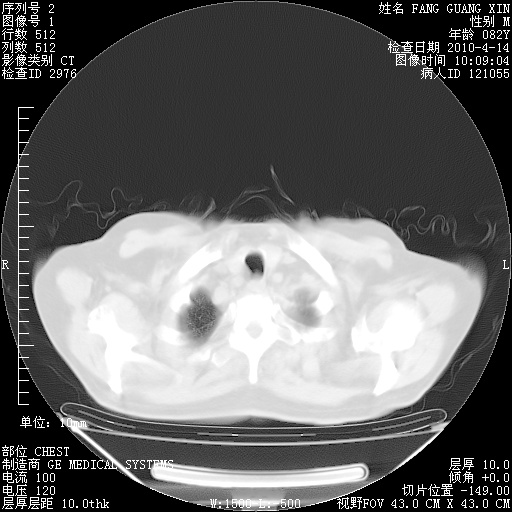

4月14日肺部CT

23.JPG

24.JPG

25.JPG

26.JPG